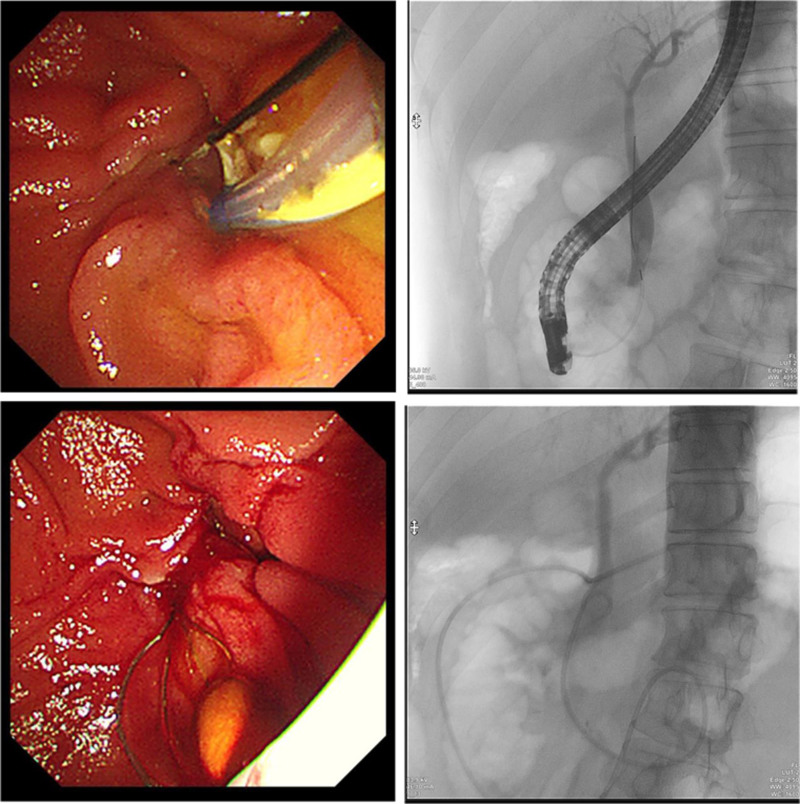

A 48-year-old male was admitted to our hospital on March 4, 2024, with intermittent abdominal pain for over a year. The pain, which occurred after consuming fatty foods, resolved spontaneously without acid reflux, nausea, vomiting, belching, fever, headache, or cough. He had a history of elevated blood glucose levels for over a year, was managed with metformin, and was allergic to apples and peach skin. Magnetic resonance cholangiopancreatography and enhanced MRI of the upper abdomen revealed the following: Cholecystitis, stones in the distal CBD with intrahepatic and extrahepatic bile duct dilation, and duodenal diverticulum. Diagnoses included: CBD stones with cholangitis, and Cholecystitis, biliary duct dilation, duodenal diverticulum. On March 6, the patient underwent ERCP with endoscopic sphincterotomy, balloon dilation of the papilla, basket retrieval of stones, balloon sweep of stones, and nasociliary drainage, with successful stone removal (Fig. 1). The surgeon, an Associate Chief Physician (equivalent to a senior consultant), performed over 1000 ERCP procedures. The endoscopic equipment included a TJF-260V Olympus duodenoscope and CV-290 processor unit.

2.1. Procedure

The duodenoscope was then advanced into the descending duodenum. A triple-lumen sphincterotome with a guidewire successfully cannulated the CBD. Aspiration yielded yellowish bile, and cholangiography revealed a dilated CBD (12 mm) containing an 8 mm × 6 mm stone. Small endoscopic sphincterotomy followed by creeping balloon dilation (8 mm) was performed. The stone was extracted using a retrieval basket and clearance was confirmed using balloon occlusion cholangiography. Under fluoroscopy, a nasociliary tube was placed in the distal CBD and transnasally secured.

POD 4: Excluding complications such as pancreatitis, cholangitis, and perforation after ERCP, further gastroscopy examination of the duodenum was performed, gastroscopy revealed a fibrin-coated ulcer adjacent to the nasociliary tube in the descending duodenum (Fig. 2). The tube was removed and pain was reduced to a visual analog scale score of 3/10.